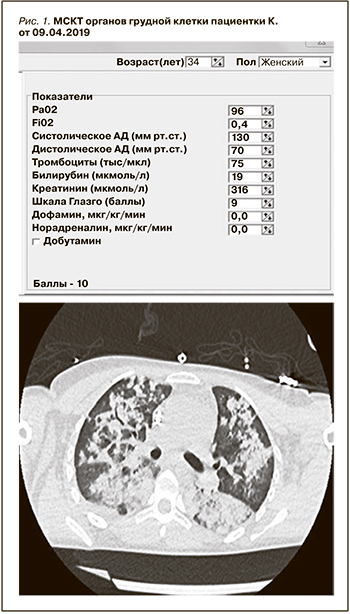

После 2-го сеанса ТРЕ лихорадка до 38,0°С, при микробиологическом исследовании БАЛ – гнойно-геморрагическое отделяемое (в посеве Staphylococcus aureus, Klebsiella pneumonia, Proteus mirabilis), по данным лабораторных исследований отмечен рост лейкоцитоза, СРБ более 300 мг/мл. Состояние расценено как поздняя нозокомиальная ИВЛ-ассоциированная пневмония на фоне геморрагического пневмонита и массивной иммуносупрессивной терапии, в связи с чем уменьшена доза кортикостероидов, прекращено проведение ТРЕ, начата поликомпонентная антимикробная терапия, включившая дорипенем, полимиксин, ванкомицин, бисептол, каспофунгин. 12.04.2019 проведено повторное КТ-исследование (рис. 2).

По сравнению с КТ от 09.04.2019 – отрицательная динамика: нижние доли обоих легких и задние сегменты верхних долей тотально безвоздушны с видимыми просветами бронхов, паренхима их уплотнена, нативной плотностью до 50 HU (признак геморрагического пропитывания), при в/в контрастировании деструктивных изменений в паренхиме легких не выявляется. В полости перикарда жидкости нет. В верхних долях обоих легких сохраняются сливные альвеолярные инфильтраты в прежнем объеме. В плевральных полостях жидкости нет. В полости перикарда минимальный выпот, не нарастает. Медиастинальные л/у множественные, умеренно увеличенные, наибольший из них размером 10,5 мм по короткой оси. В просвете трахеи и главных бронхов патологических включений не выявлено. С обеих сторон адекватно установленные ЦВК.

Заключение: КТ-картина обширного острого альвеолярного повреждения легких с тотальной безвоздушностью паренхимы нижних долей обоих легких, нарастания выраженности уплотнений, наиболее вероятно за счет геморрагического пропитывания, менее вероятно – пневмоническая инфильтрация. По сравнению с КТ-исследованием от 09.04.2019 динамика отрицательная.

С 27.04.2019 повторных приступов генерализованного тонико-клонического судорожного синдрома не регистрировалось. На фоне проведенной терапии восстановилось сознание, регрессировали признаки дыхательной недостаточности (рис. 3).

По сравнению с КТ от 12.04.2019 – выраженная положительная динамика в виде дальнейшего уменьшения объема консолидации в нижних долях обоих легких, почти полного восстановления нормальной пневматизации верхних долей. Новых патологических изменений нет. Альвеолярные инфильтраты в верхних долях с признаками начальной резорбции. В полости перикарда – минимальное количество жидкости. Появился выпот в плевральных полостях (180 мл справа, 120 мл слева). Медиастинальные л/у множественные, умеренно увеличенные, наибольший из них размером 10,5 мм по короткой оси. В просвете трахеи и главных бронхов патологических включений не выявляется.

Заключение: КТ-картина разрешения альвеолярного повреждения легких в стадии неполного восстановления.